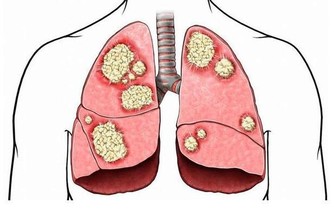

二、心梗

心梗被稱為“迅捷的殺手”,患者常常在很短時間內,就被奪去了生命。

其實,雖然心梗從發作到猝死只有短短幾分鐘,但很多患者在心梗發病前,是有一些預警症狀的,

這些症狀往往會持續一兩天,如果在這時候儘早干預,就能有很大概率挽救生命。

心梗前兆如下:

1、長期高血壓、冠心病的老年人,無緣無故拉肚子,吃藥也不見好轉。

很多心梗,會表現為腹部不舒服。

2、在勞累或運動後,出現肩膀疼痛、後背疼痛、牙齒疼痛、喉嚨發緊等症狀,

且這些症狀會隨著運動的增多而加劇。

3、心絞痛、胸悶氣短等症狀在近期加劇。

例如原本走1公里才胸悶氣喘,現在走500米就不行了,那要趕快去醫院檢查。

4、突然出現心慌和嚴重憋氣的情況,吃藥也不管用。

5、突然出現嚴重胸痛,並伴有大汗淋漓的情況。